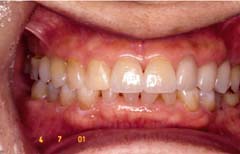

■ホームブリーチング■

施術前

施術後

「ホームブリーチング」とは歯の色を明るく・白くする治療方法です。

診療室で治療をする「オフィスブリーチング」と自宅で行う「ホームブリーチング」があります。

当院 では「ホームブリーチング」をお勧めしています。

具体的には、ご自分専用の薄型のトレーにブリーチング・ジェルを塗布し寝ている間にはめて歯を白くする方法です。

早い人で2週間目から白さを実感できます。

ゆっくりジェルを浸透させることで「自然な白さ」を手に入れられることができます。